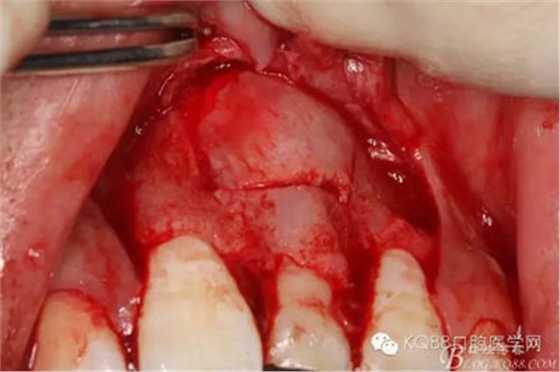

圖13.超聲骨刀清理周圍組織,21有Ⅰ°松動

圖14.牙冠周圍滲血多,無法粘結(jié)托槽。位置也高,隨與家屬溝通,暫時保留乳Ⅰ。待21初步穩(wěn)定,再考慮正畸牽引

圖15.輕輕的把21牙冠牽引至乳Ⅰ根尖方向,并擺正牙冠位置。(拔苗助長)

圖16.牙冠上方覆蓋膠原蛋白膜

圖17.骨壁重新覆蓋回去